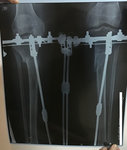

Дата операции 23.05.2017г.

Дата снятия аппаратов 16.10.2017г.

Срок лечения 142 дня.